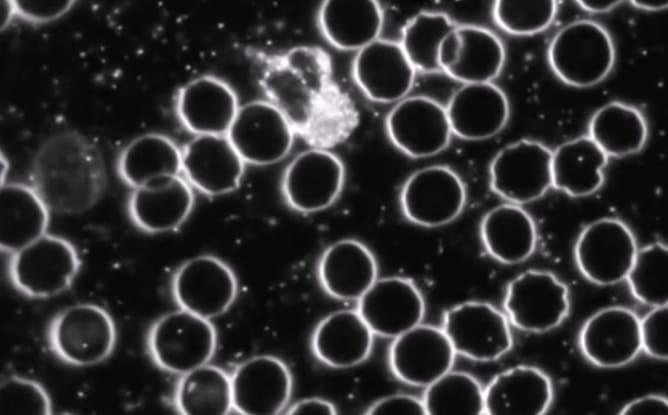

La microscope à fond noir est un outil avec lequel on observe une goutte de sang fraîche (prise au bout du doigt), sans la colorer, grâce à un éclairage particulier. Cela permet de voir les cellules vivantes telles qu’elles sont. Ce type d’examen donne une idée générale de la santé, peut montrer la présence de certains micro-organismes, révéler si les globules rouges ont une forme anormale (ce qui peut indiquer un manque de nutriments), et parfois détecter des signes d’infections bactériennes ou fongiques. C’est un outil génial pour orienter le diagnostic des troubles dont souffrent les patient-es et pour toutes celles et ceux qui souhaitent améliorer leur santé!